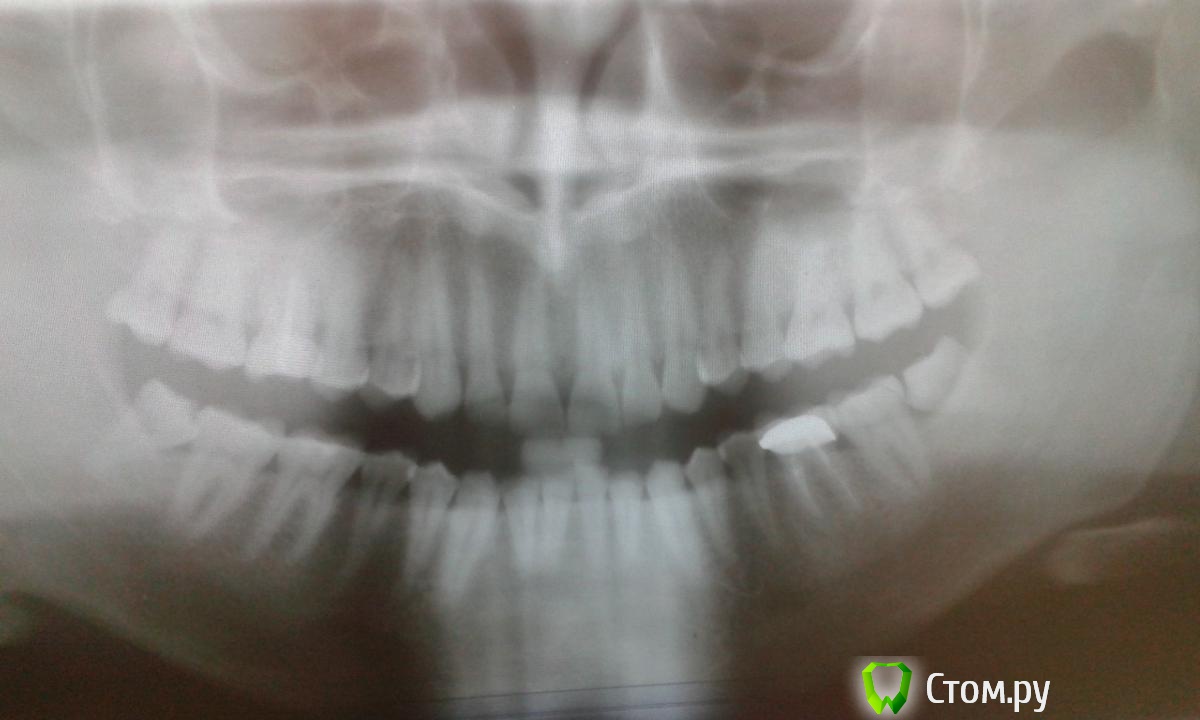

g_kot Опубликовано 24 января, 2014 Поделиться Опубликовано 24 января, 2014 Добрый день. Сделал панорамный снимок и записался к имплантологу... но прием только через неделю. Поэтому не терпится узнать что у меня там.Суть проблемы в том что на верхней 6ке (отмечена) стрелочкой хронический периодонтит, коронки почти нет и предложено удаление. Нужен ли там синус лифтинг. И еще заметил темное пятно на контакте 7 и 8 (тоже стрелочкой отмечено) Кариес? Снимок если не информативен - попробую сделать по другому. Ссылка на комментарий

g_kot Опубликовано 24 января, 2014 Автор Поделиться Опубликовано 24 января, 2014 Так лучше видно? Ссылка на комментарий